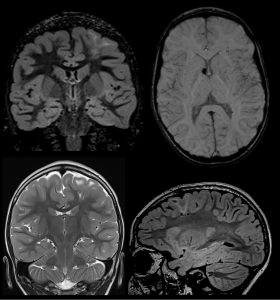

- Niño de 4 años en estudio por crisis comiciales.

La Esclerosis Tuberosa (ET) es un síndrome neurocutáneo con herencia autosómica dominante caracterizado por una amplia variedad de lesiones hamartomatosas multiorgánicas y manifestaciones neurológicas.

Su triada clínica característica consiste en lesiones cutáneas, retraso mental y convulsiones.

Se han establecido 11 criterios diagnósticos mayores y 6 menores. La presencia de dos criterios mayores o de un criterio mayor y dos criterios menores se considera suficiente para el diagnóstico definitivo. El diagnóstico diferencial se hace con las displasias corticales y la infección congénita por CMV.

Los túberes corticales (criterio mayor), que aparecen en más del 95% de casos, son lesiones hipointensas en T1 e hiperintensas en T2, que realzan ocasionalmente con contraste.

Los nódulos subependimarios (criterio mayor), aparecen en más del 95% de casos, son lesiones que se disponen en los márgenes laterales de los ventrículos laterales y frecuentemente están calcificadas.

Los astrocitomas subependimarios de células gigantes (criterio mayor), se localizan típicamente en el agujero de Monro, y presentan un crecimiento lento y tamaños superiores a un centímetro.

Las bandas de migración radial en la sustancia blanca (criterio menor), reflejan una alteración en el proceso de migración de las neuronas desde la matriz germinal subependimaria hasta la corteza y se observan en alrededor del 20% de pacientes, presentando hiposeñal en T1 e hiperseñal en T2.

Este caso ilustra la posibilidad de hacer el diagnóstico de ET en base a la presencia únicamente de hallazgos neurorradiológicos, preferentemente mediante RM, incluso sin mutaciones moleculares identificables, situación que se da un alrededor de un 15-20% de pacientes.